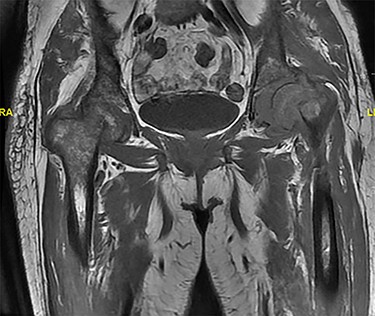

The patient was then referred to an outpatient physical therapy center to resume her physiotherapy. The patient achieved full weight bearing and excellent range of motion within 2 months postoperatively. Implants remained in good position showing no signs of loosening on x-rays (Fig. 4) on the ninth month visit, and she denied any pain with walking and had excellent range of motion at the time.

(A) Left (L) view of the implant in position; (B) Pelvic X-ray showing the implant in position.